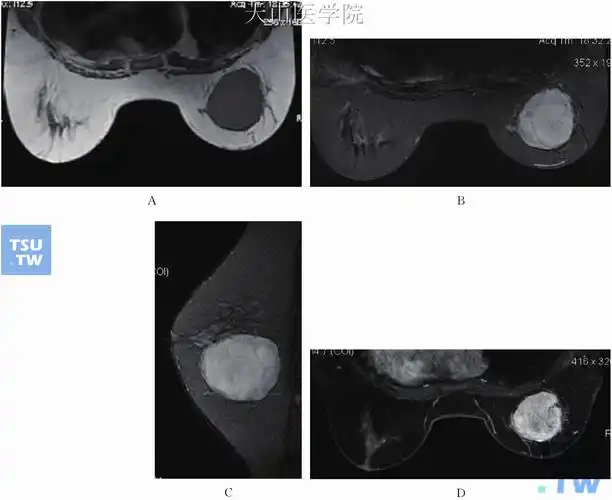

磁共振乳腺成像